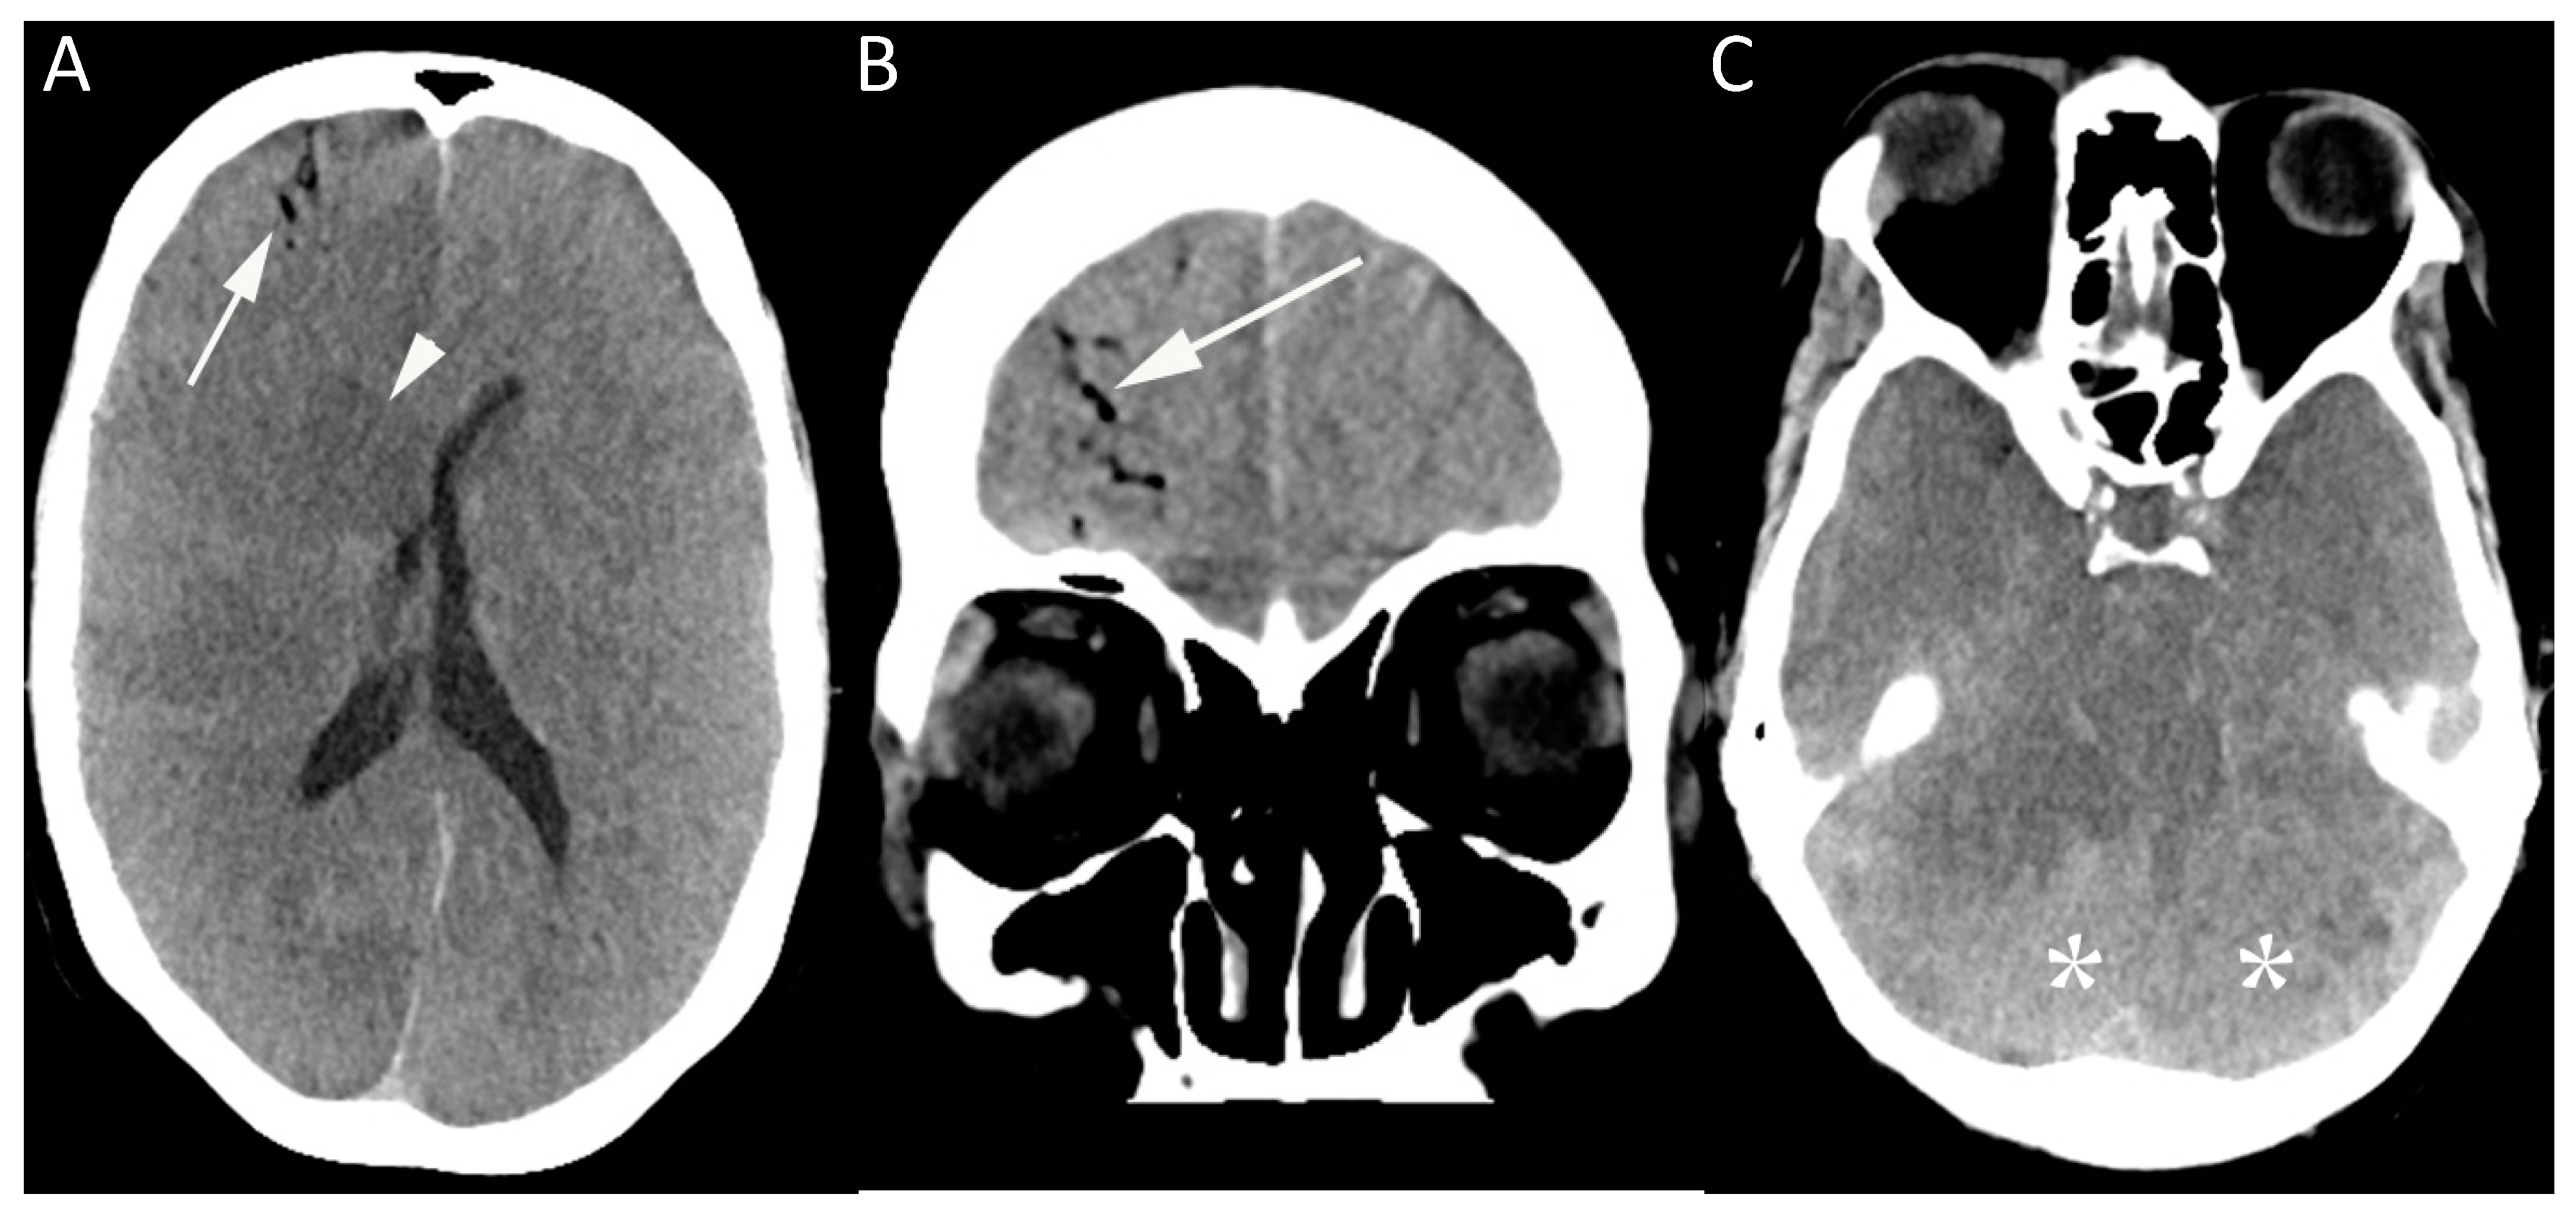

Figure 1.

This image shows a computed tomography (CT) brain of a 50-year-old female in the medical intensive care unit who became unresponsive shortly after removal of an internal jugular line. CT brain (A–C) was performed showing gas within the right frontal lobe in distribution, suggesting an intravascular location (arrow, A and B), together with diffuse loss of gray-white matter differentiation, most prominently in the central deep nuclei (arrowhead). There was evidence of mass effect, with effacement of the basal cisterns (C), and the dense cerebellum sign (*) related to relative sparing of the cerebellar hemispheres.